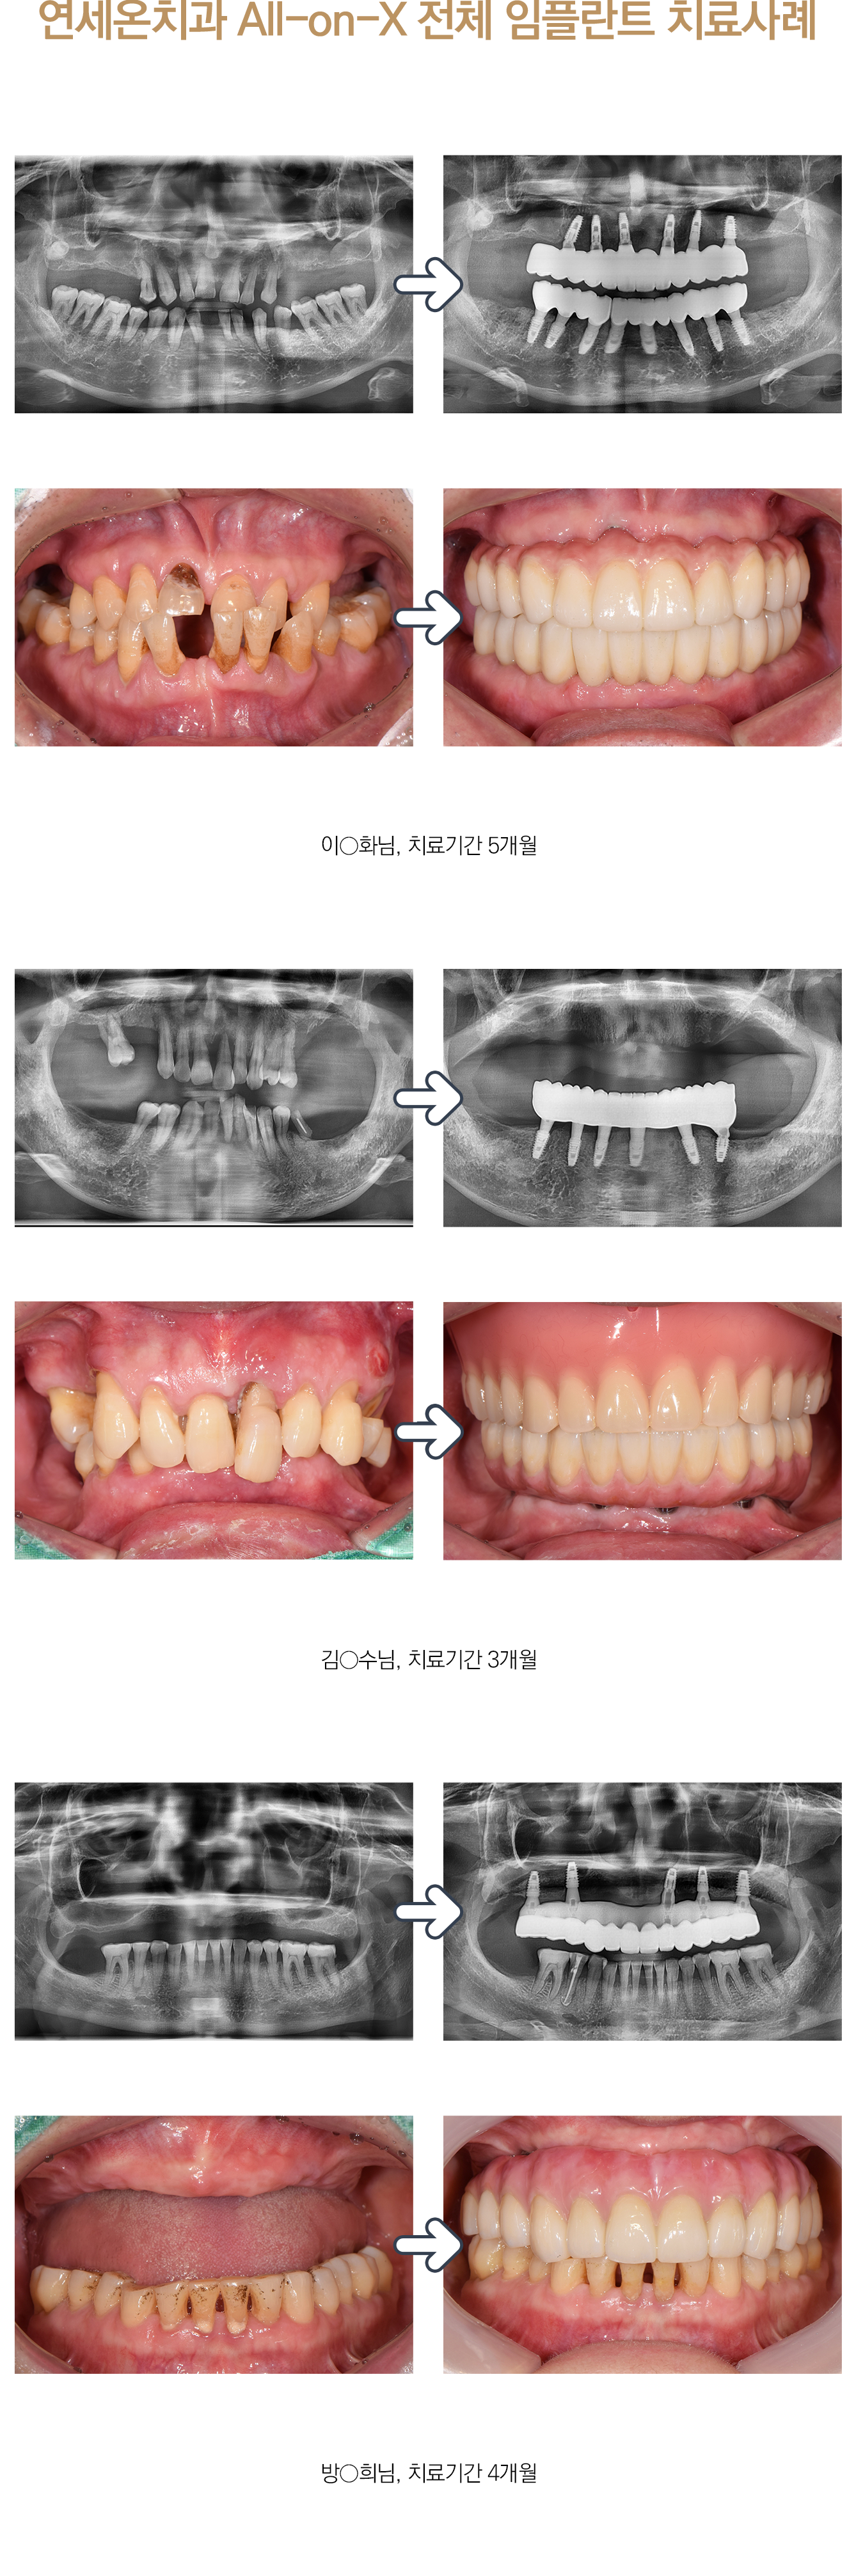

본 사진은 환자분의 동의하에 게재하였습니다.